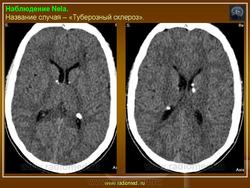

Туберозный склероз, или синдром Бурневиля - Прингля.

Приложения:

1.tu_.slayd184.jpg2.tu_.slayd185.jpg

Встречаются и аномалии развития извилин мозга в виде микро- и пахигирии. Заболевание чаще носит спорадический характер. Бляшки достигают диаметра 5-20 мм. В коре больших полушарий и мозжечка иногда могут быть обнару­жены пластинчатые тельца, напоминающие амилоид. Происходит дегенерация клеток коры. При КТ-исследовании головы нередко можно выявить кальцифика-ты и глиальные узелки в паравентрикулярной области, субэпендимарно вдоль на­ружных стенок боковых желудочков, в зоне межжелудочкового отверстия Мон­ро, реже - в мозговой паренхиме. На М РТ головного мозга в 60% выявляются гипотеденсивные очаги в одной или обеих затылочных долях, которые расце­ниваются как участки неправильной миелинизации (Козлов А.В., 2002).